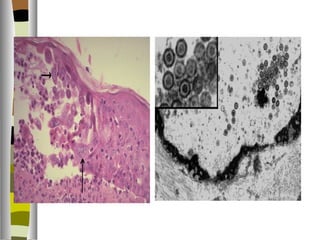

   I. citopática-citoproliferativa: por daño viral a las células del

húesped sin respuesta inflamatoria del huésped,

   muestra cuerpos de inclusión CMV, herpesvirus forma

ampollas.

   1. Virus herpes simple de tipos 1 y 2. Son v. de gran

   En las infecciones primarias se replican y causan lesiones

vesiculares de la piel y membranas mucosas.

   Inclusiones intracelulares color rosado ( Cowdry A ) que

contienen viriones, también dan sincitios multinucleados

diagnósticos en los frotis.